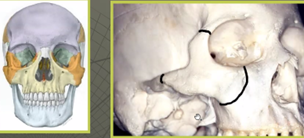

o 5 infästningar

o Effekter kan bli: asymmetri, hak margo infraorbitale, hak crista infrazygomatica, nedsatt ögonrörlighet – diplopi, enopthalmus (injunket öga), känselbortfall, nedsatt gapförmåga

Vilken fraktur handlar det om?

A

Os zygomatocusfraktur